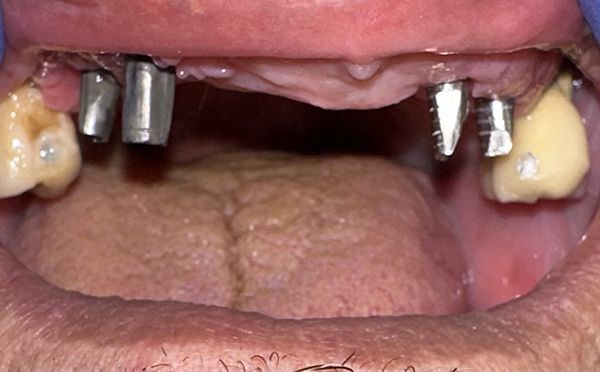

UN'EMERGENZA DENTALE / FOTO 4

ButtonMonconi grezzi ricostruiti con tecnica indiretta. Verranno perfezionati successivamente, al momento lo scopo è quello di garantire un'estetica decorosa alla paziente.